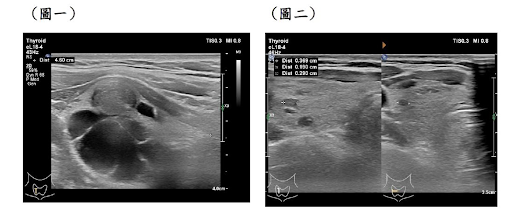

△圖一治療前圖二治療後影像。

黃嘉崙醫師表示,根據複雜多隔腫瘤的特點,這類腫瘤包含兩個主要部分;一種是囊性部分,有多個分隔腔室,內部含有水樣或膠狀液體,射頻消融難以解決;另一部分是腫瘤內的結節性表現。複雜的多間隔甲狀腺腫瘤,在甲狀腺腫瘤中是難治腫瘤之一,若要考慮到安全性、有效性和微創美觀更是難上加難。

在這些已確認為良性組織之病例,黃醫師等甲狀腺腫瘤微創消融團隊操作超音波導引抽吸出甲狀腺腫瘤內液體,並於每腔室中注入高濃度乙醇注射。完成一系列高濃度乙醇注射後,進行高頻設射甲狀腺腫瘤消融術,並定期評估這些複雜型甲狀腺腫瘤體積特徵和變化。

三總澎湖分院黃嘉崙醫師帶領之甲狀腺腫瘤微創團隊結合乙醇注射及高頻設射甲狀腺腫瘤消融術序列混成治療,經過一年的追蹤,這些複雜型多間隔甲狀腺腫瘤與初始體積相比能達九成五之體積縮小率,有著傑出的創新結果。

拜醫療科技進步所賜,目前甲狀腺腫瘤射頻消融手術 (Radiofrequency Ablation of Thyroid)適合用於良性結節,甲狀腺微小癌或甲狀腺癌復發等患者。同時擁有許多優勢,微創、美觀和快速腫瘤縮小,是複雜多間隔甲狀腺腫瘤的創新混合分期管理的優點,將成為複雜型多間隔甲狀腺腫瘤之嶄新治療模式。